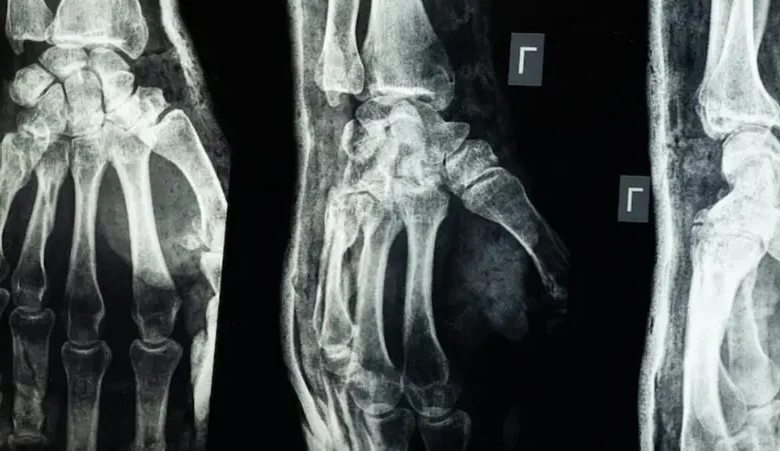

“غراء عظمي”.. ابتكار صيني لعلاج الكسور في 3 دقائق

أعلن فريق بحثي في مقاطعة تشيجيانغ شرق الصين عن ابتكار طبي جديد يتمثل في “غراء عظمي” قادر على معالجة الكسور وتركيب الشظايا العظمية خلال ثلاث دقائق فقط، في خطوة وُصفت بأنها اختراق علمي في عالم جراحة العظام، بحسب ما نقل موقع “إن دي تي في” NDTV.

وأكدت الاختبارات المعملية أن Bone-02 نجح في تحقيق نتائج جيدة من حيث السلامة والفعالية. وفي إحدى التجارب، أُجريت العملية في أقل من 180 ثانية (ثلاث دقائق)، بينما كانت طرق العلاج التقليدية تتطلب وقتاً طويلاً لزرع صفائح فولاذية ومسامير.

وبحسب الاختبارات المعملية، تمكن الغراء من تحقيق قوة ربط تفوق 400 رطل، وقوة قص تبلغ نحو 0.5 ميغاباسكال، وقوة ضغط تقارب 10 ميغاباسكال. كما أظهرت التجارب على أكثر من 150 مريضاً نتائج ناجحة، ما يعزز احتمالية أن يصبح بديلاً للزراعات المعدنية التقليدية التي تُستخدم في تثبيت العظام. كما يقول العلماء إنه قد يقلل أيضًا من مخاطر العدوى.